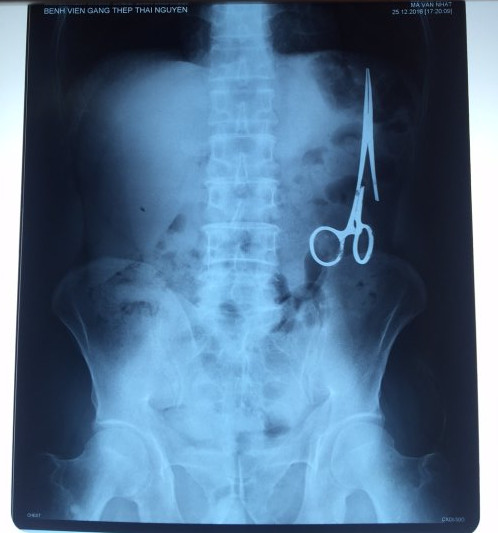

遺留在病人腹中的剪刀

據(jù)越南青年報(bào)1月2日?qǐng)?bào)道,在越南首都河內(nèi)醫(yī)療專家的幫助下,越南東北部的太原省(Thai Nguyen)鑄鋼醫(yī)院的醫(yī)生日前從54歲患者M(jìn).V.N腹中取出一把醫(yī)用剪刀。這把剪刀是此前曾為M.V.N手術(shù)的醫(yī)生遺留的,已經(jīng)在其腹中待了18年時(shí)間。

醫(yī)務(wù)人員表示,這把剪刀遺留在病人腹部左側(cè),與結(jié)腸緊挨著。剪刀的把手已經(jīng)生銹,部分器官也已經(jīng)與剪刀粘連起來。但在過去多年中,M.V.N沒有任何不適感覺,也從未因?yàn)榱粼诟怪械募舻兑l(fā)的相關(guān)問題去看過醫(yī)生。直到2016年12月,M.V.N因?yàn)樵庥隽艘粓鲕嚨湥诺借T鋼醫(yī)院進(jìn)行身體檢查。

超聲波檢查顯示,M.V.N的腸子中有個(gè)奇怪物體,看起來就像醫(yī)用剪刀。M.V.N證實(shí),他曾于1998年6月份在北江省綜合醫(yī)院接受手術(shù),在此后也從未進(jìn)行過任何手術(shù)。近來,他感到腹部有些疼痛,并試圖通過服用藥物治療。12月27日,M.V.N回到北江省綜合醫(yī)院再次進(jìn)行超聲波檢查,顯示其腹部的確存在怪異物體。